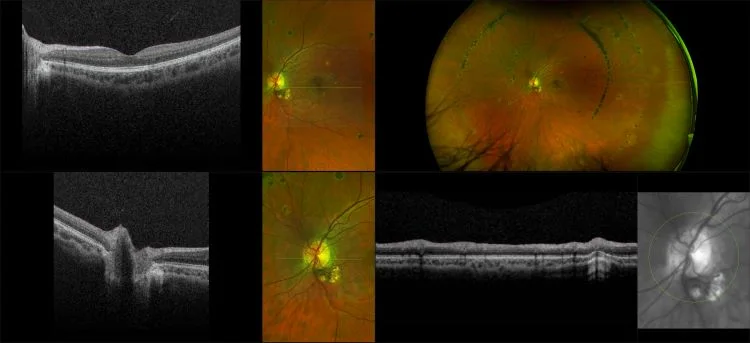

optomap images representing other retinal disease not found in common categories of pathology.